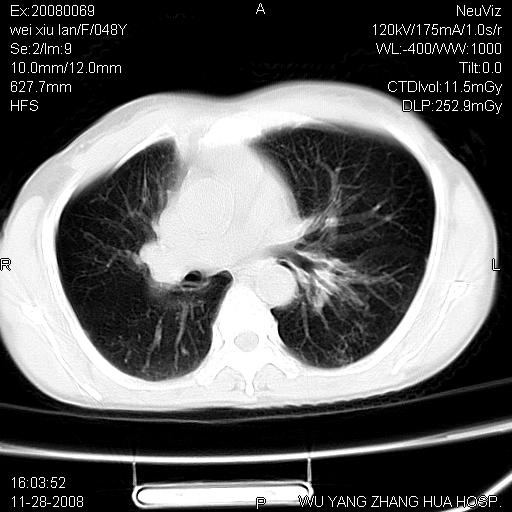

标题: CT16847:女,48岁,咳嗽,发热两日,平常偶有上腹部不适。 [打印本页]

标题: CT16847:女,48岁,咳嗽,发热两日,平常偶有上腹部不适。

能否考虑食管裂孔疝?请老师们多多指教。

胃、脾脏及部分肠管明显升高,并压迫心脏移位,

首先考虑:左侧膈疝。

左侧胸腔内见胃肠及脾脏影

支持膈疝

支持左侧膈疝,心脏受压右移.

这个是左侧膈膨升伴不完全性胃翻转,手术将松弛的左横膈膜折叠缝合即解决问题。

左下肺不张、膈膨升,胸腔胃